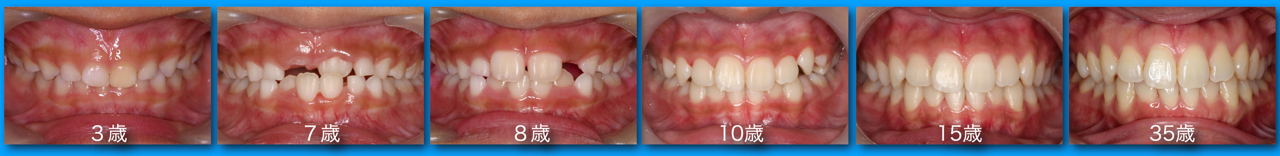

須貝歯科医院では患者さんのお口の中の写真を撮り、説明や経過観察に役立てています。手鏡で口の中を見せられ説明されてもなかなかわからないものですが、写真を見ればすぐわかるものも多くあります。またメインテナンス時に患者さんが来院し不調を訴えられたときに以前の写真があればどこが変化したのかがわかりやすくなります。何年かぶりに来院した患者さんの写真を見比べてあまりの変化にお互いびっくりすることもあります。

歯にものがはさまるという患者さんの写真です。歯の一部が欠けてしまい金属との間に隙間ができているのがはっきりわかります。素人の患者さんが見ても治療が必要であることがわかると思います

入れた歯の噛み合わせがおかしい、物がよくはさまる、糸楊枝が引っかかるなどの経験をしたことのある方も多いと思います。これは金属の被せ物や詰め物の精度の問題です。下の左右のレントゲン写真を比べてみましょう。レントゲンの中で白く抜けているのは金属の詰め物です。左側のレントゲンの詰め物は自分の歯と合っていないのがわかります。治療後の右側レントゲンの詰め物は歯とピッタリ合っているように見えます。糸楊枝を入れてもどこも引っかかりませんし違和感もありません。いつもこのように製作することが理想ですがそのためには衛生士が歯と歯肉をきれいにし、歯科医がきれいに歯を削り、歯形を取り、技工士が丁寧に補綴物を製作というすべてのステップをしっかり行うことが必要です。コストも労力もかかることですが須貝歯科医院ではすべてを院内で行うことで精度の高い物を作るように努力しています。残念なことですが現在の保険診療では完全な赤字部門で院内で賄うことで何とか頑張っています。保険で使用できる金属があまり良い物ではないこともあり、できるだけ保険外の適切な材料を使用して被せ物や詰め物を作っていただけるように患者さんにはお願いしています。